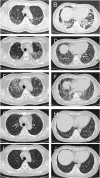

Dermatomyositis (DM) positive for anti-melanoma differentiation-associated gene 5 (MDA5) antibodies, mainly when linked with rapidly progressive interstitial lung disease (RP-ILD), is considered a refractory disease. Our report describes a critical case of clinically amyopathic dermatomyositis (CADM) with RP-ILD that tested positive for both anti-MDA5 and anti-Ro-52 antibodies. The patient showed a limited response to a combined therapy regimen of prednisone, iguratimod, and tacrolimus. However, after adjunct therapy with mycophenolate mofetil (MMF), the patient's condition was controlled, his serum KL-6 levels decreased, and anti-MDA5 antibodies became negative. During the 68-week follow-up, the patient's condition remained stable, with a satisfactory quality of life. This report also discusses the potential role of inflammatory cytokines in the pathophysiology of CADM and RP-ILD. Further research is required to confirm these results and investigate the application of MMF in maintenance therapy for CADM-associated RP-ILD.